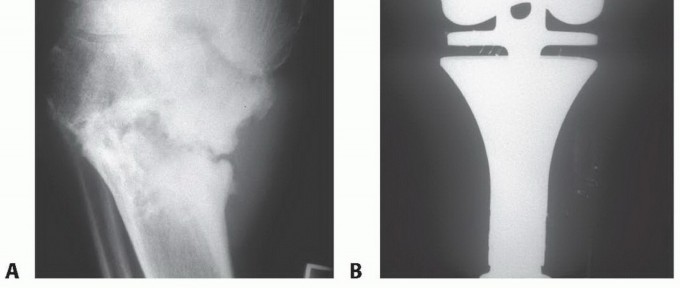

الكسور غير المبررة (الكسور المرضية):

- السبب: قد يؤدي الورم إلى إضعاف العظم، مما يجعله عرضة للكسر حتى مع إصابة طفيفة أو بدون سبب واضح.

- الأهمية: هذا العرض يجب أن يدفع إلى البحث عن السبب الأساسي لضعف العظم.

| الكسور المرضية | كسر العظم نتيجة إصابة طفيفة جدًا أو بدون سبب واضح، بسبب ضعف العظم. | علامة قوية على ضعف العظم، غالبًا ما تكون بسبب ورم كامن. |

الاستئصال الواسع (Wide Excision):

إزالة الورم مع هامش واسع من الأنسجة السليمة المحيطة لضمان إزالة جميع الخلايا السرطانية. قد يتطلب ذلك إعادة بناء العظم باستخدام طعوم عظمية أو بدائل صناعية.

الجراحة الحافظة للأطراف (Limb Salvage Surgery):

تهدف إلى إزالة الورم مع الحفاظ على الطرف المصاب. تتضمن إزالة الجزء المصاب من العظم واستبداله بطعم عظمي، أو مفصل صناعي، أو طرف اصطناعي داخلي (Endoprosthesis). تتطلب مهارة جراحية عالية وتخطيطًا دقيقًا.

البتر (Amputation):

في الحالات التي يكون فيها الورم كبيرًا جدًا، أو انتشر بشكل واسع، أو أصاب الأوعية الدموية والأعصاب الرئيسية، قد يكون البتر هو الخيار الوحيد لإنقاذ حياة المريض ومنع انتشار السرطان.